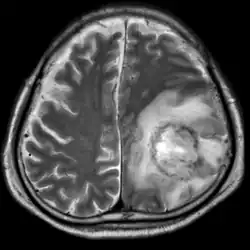

T2-weighted MRI showing a necrotic brain abscess caused by Acanthamoeba.